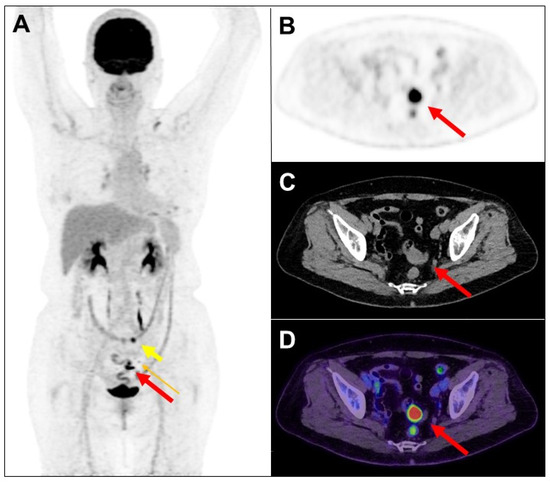

F-18 fluorodeoxyglucose (FDG) is excreted in part by the gastro-intestinal tract, with accumulation expected normally in the stomach and intestines. These physiologic sites of FDG accumulation may be confused with malignant lesions, and similarly increased FDG accumulation in malignant lesions may be interpreted as unrelated to cancer. A 75-year-old woman had a history of left breast adenoid cystic carcinoma following neoadjuvant chemotherapy and partial mastectomy. The pathology stage was pT2N0, and the Ki-67 index was 5%. Four years later, the patient’s left chest wall recurred and received excision. More than two weeks later, she received FDG positron emission tomography (PET)/computed tomography (CT) scan. The maximum-intensity projection view of PET image (A) revealed a focal intense FDG accumulation in the sigmoid (long thick arrow: red color), a focal mild FDG uptake in the pericolic lymph node (0.6 cm, long thin arrow: orange color), and a focal increased FDG accumulation in the transverse colon (short thick arrow: yellow color). Transaxial views of PET (B), CT (C), and PET/CT fusion (D) images showed a possible nodule in the sigmoid (long thick arrow: red color).